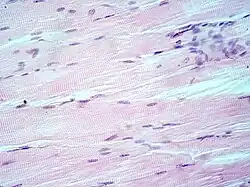

Micrografía de un corte transversal de músculo esquelético estriado. En la periferia de cada célula sincitial se observan varios núcleos. | ||

- Músculo esquelético

El músculo esquelético es considerado un verdadero sincitio anatómico, pues cada célula presenta múltiples núcleos, originada por la fusión de múltiples células. Los mioblastos comienzan a multiplicarse, influidos por factores de crecimiento como el FGF. Los receptores integrinas de las fibronectinas y otras moléculas como las cadherinas los obligan a reconocerse, alinearse y adherirse, para posteriormente fusionarse en células musculares sincitiales. Este último proceso está mediado por meltrinas —unas metaloproteasas—.[12] En cultivo, los mioblastos forman el sincitio al proliferar y fusionarse mientras producen proteínas contráctiles. Este proceso es cooperativo, de tal forma que la fusión celular altera el medio de cultivo para inducir la fusión de otros mioblastos.[29]

El sincitio del músculo esquelético permite una rápida contracción coordinada de los músculos en toda su longitud. El potencial de acción se propaga a lo largo de la superficie de la fibra muscular desde el punto de contacto sináptico con la neurona motora.[30] En estados patológicos como la miopatía, la presencia de sincitio permite la viabilidad muscular, porque los focos de necrosis de una parte del músculo esquelético no resultan en la necrosis de las secciones adyacentes de esa zona ya que estas regiones tienen su propio material nuclear, aunque algunos de los segmentos supervivientes queden sin inervación por la pérdida de continuidad con la unión neuromuscular.[31]